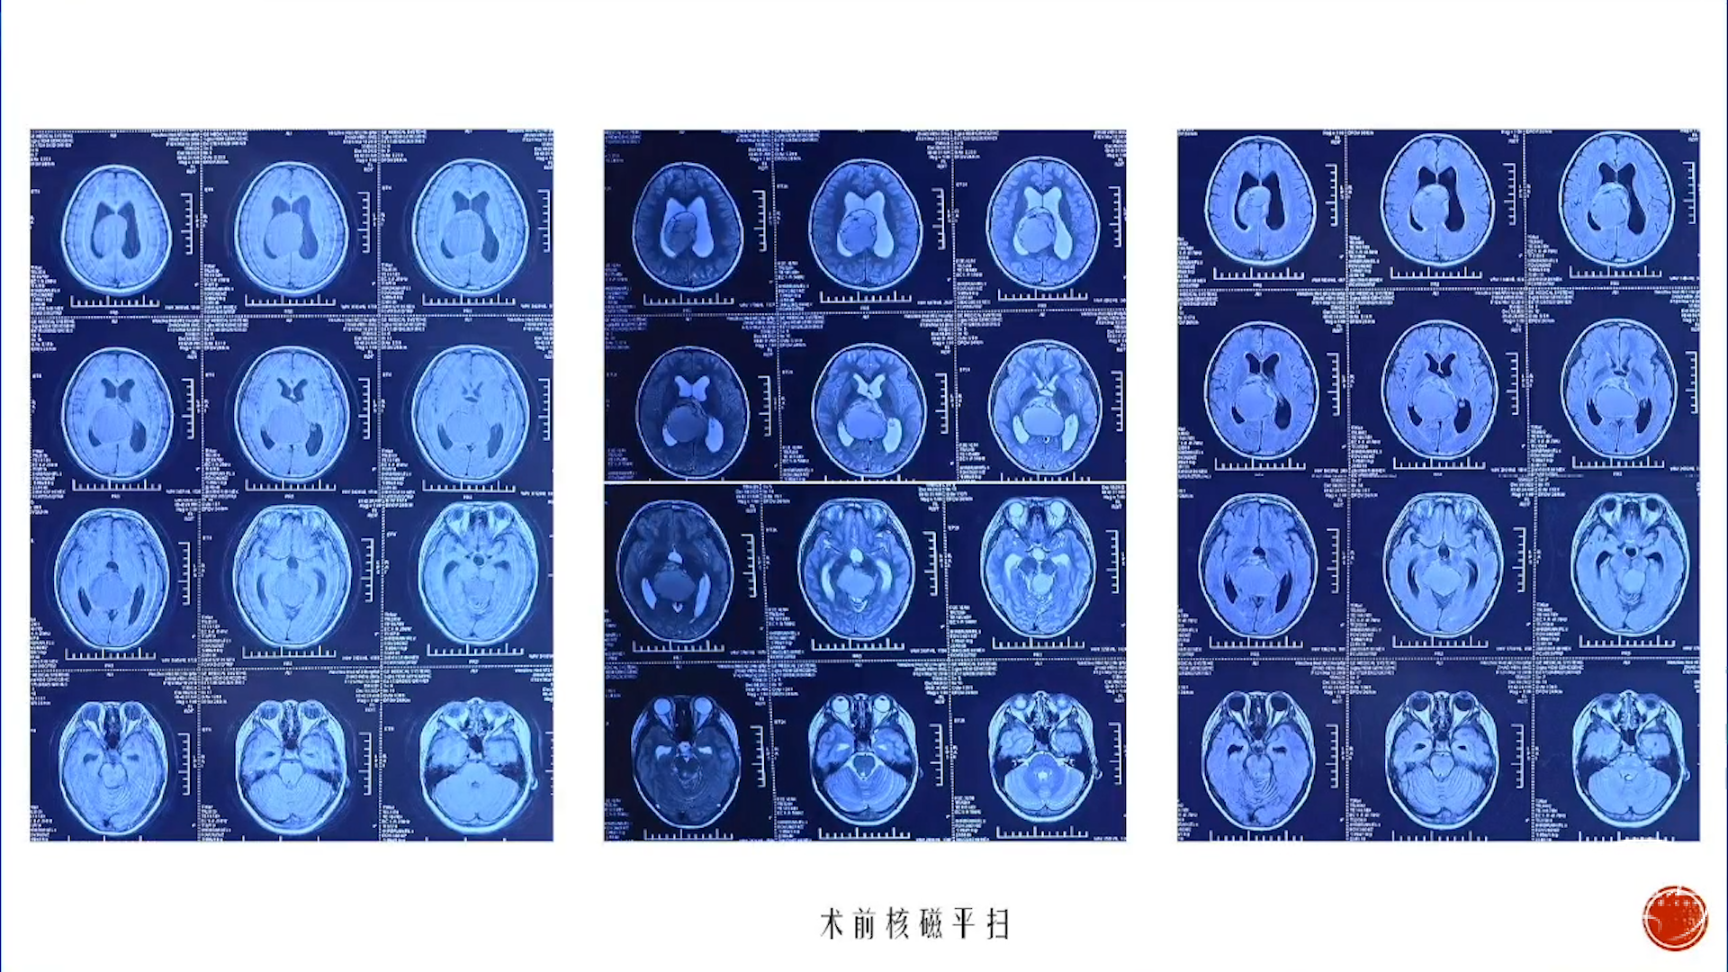

小脑星形细胞肿瘤